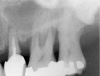

After penetration into the sinus is achieved, a sterile amalgam carrier is used two times to deliver a radiopaque bone substitute into the osteotomy. Then the osteotome used to infracture the subantral floor is lubricated with saline and inserted into the osteotomy until the stop on the osteotome reaches the alveolar crest. This pushes the bone substitute up under the sinus membrane and elevates it. Two more carriers of bone substitute are delivered in the same manner. This will provide around 2 mm of bone height in the sinus (four carriers provide around 2 mm of bone height). A radiograph is then taken to verify that the membrane was elevated, and the bone graft should appear as a dome (Figure 4). If the sinus floor has not been penetrated despite the impression that it was, the bone-graft material may have been pushed laterally. If this occurs, there will be no dome on the radiograph, but, rather, increased osseous density on the lateral aspect of the osteotomy. If this occurs the osteotomy needs to be deepened.

Figure 4  After infracturing the subantral wall with a 3.5-mm osteotome, bone was added and the presence of a dome was confirmed with a radiograph.

Figure 4